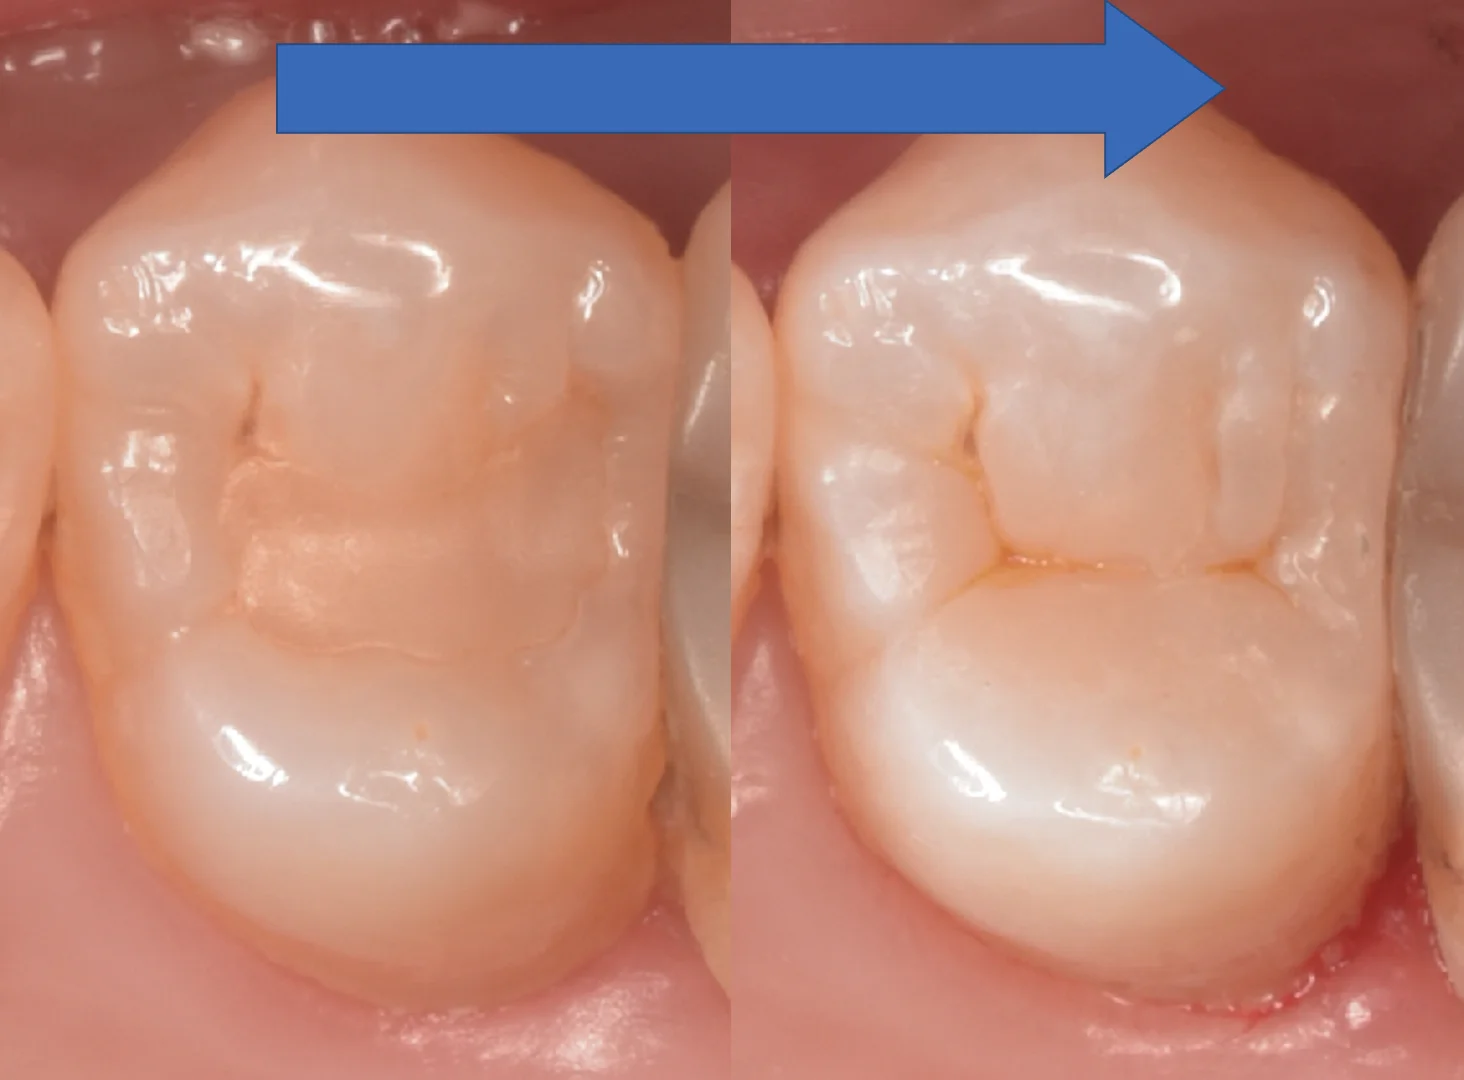

術前術後です。

非常に難易度が高かったですが、いい仕上がりになってよかったです!